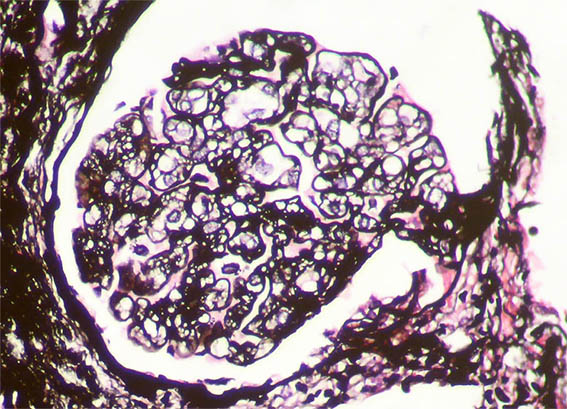

Figure 5. Methenamine-silver stain, X400.

Figure 6. Methenamine-silver stain, X400.

Figure 7. Methenamine-silver stain, X400. Mesangiolysis.